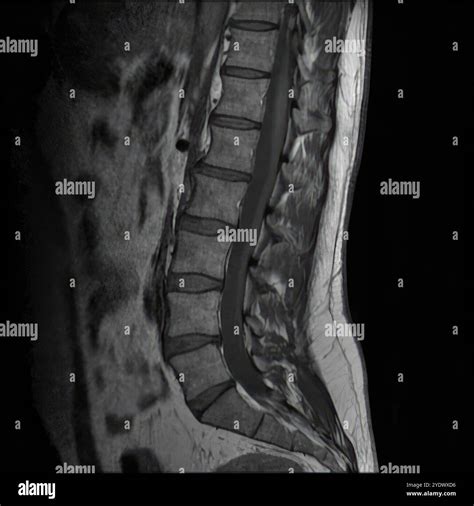

When you experience persistent neck pain, radiating discomfort into your arms, or unexplained numbness, your physician may recommend an MRI of the cervical spine. This advanced diagnostic imaging tool is the gold standard for visualizing the delicate structures of your neck, including the spinal cord, nerve roots, and the vertebrae themselves. Unlike X-rays, which primarily show bones, an MRI uses powerful magnetic fields and radio waves to create detailed, cross-sectional images of both hard and soft tissues. Understanding what this procedure entails can help alleviate anxiety and ensure you are prepared for your appointment.

The cervical spine comprises the top seven vertebrae of your spinal column, labeled C1 through C7. This area is highly complex and functionally vital, as it protects the spinal cord and allows for a wide range of head and neck movement. An MRI of the cervical spine provides a comprehensive view of several critical components:

Doctors order this scan to investigate symptoms that suggest nerve compression or structural abnormalities. It is a highly sensitive diagnostic tool that helps differentiate between various conditions. Common reasons for ordering this scan include:

The primary advantage of using an MRI of the cervical spine over other imaging modalities is its superior soft-tissue contrast. Because the spinal cord and nerve roots are essentially soft tissue structures, standard X-rays are largely ineffective at visualizing them. By utilizing contrast agents in some cases, radiologists can also identify inflammation or vascular issues that are not visible on plain films. Furthermore, MRI involves zero ionizing radiation, making it a safer long-term option compared to repeated CT scans or X-rays.